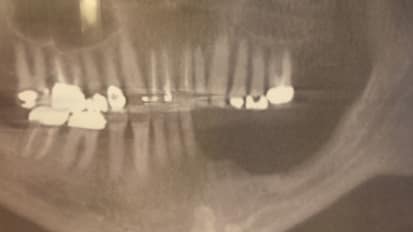

Alexander Pazoki, D.D.S.,M.D.,F.A.C.S., Director of the Johns Hopkins Division of Oral and Maxillofacial Surgery and Dentistry, and Assistant Professor of Otolaryngology–Head and Neck Surgery, presents the case of a 14-year-old boy who injured his jaw as a child and wasn't verbal or able to eat most solid foods.  As the boy grew older, his lower jaw became locked in place, limiting his ability to open his jaw more than one centimeter.